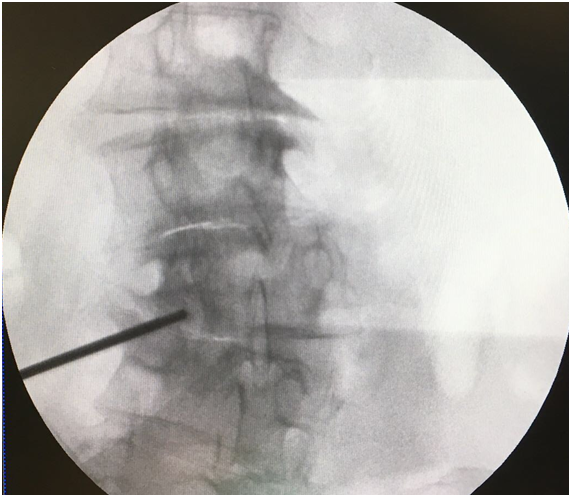

A transforaminal (TF) block was proposed at L2, L3, and L4 on the left side. After explaining the technique and its possible complications, which include the risks of infection, bleeding, and allergic reactions, oral and written consent was obtained, and the nature of the technique was explained to the patient, i.e. to perform a diagnostic block to determine the source of her pain. The technique was performed in the operating room on an outpatient basis, with standard monitoring according to SEDAR [Spanish Society of Anesthesia, Recovery, and Pain Therapy] standards (including EKG, O2 saturation, and non-invasive blood pressure tests) and radiological monitoring. The interventionist located the treatment sites with the patient lying in the prone position, using an abdominal pillow to reduce lumbar lordosis. During the procedure, a Yale 22G spinal needle was used for all treatment sites. The area was cleaned with chlorhexidine solution and misted so that the surgical field was completely sterile, with the area to be treated left exposed. A TF block was performed at the level of L2 without difficulty, although the TF block at the level of L3 was very difficult due to the patient’s anatomy, which presented with a lateral displacement of L3 and abundant osteophytes on the vertebral body, making it very difficult to visualize the entry point through the foramen. For this reason, it was deemed more appropriate to enter through the L3-L4 facet joint. In order to perform the block at this location, the C-arm of the fluoroscope was tilted obliquely until the spinous process was brought to the contralateral pedicle axis, or until the superior articular process could be seen in the middle part of the intervertebral disc, forming the famous “Scottie dog” sign, at an oblique inclination of approximately 20-30º; the double contour of the intervertebral disc was corrected with a craniocaudal inclination of the C-arm. After this maneuver, the X-ray was inclined craniocaudally (20º) to separate the iliac crest and allow entry into the foramen, according to the usual technique.13 Given the impossibility of visualizing the entry point, the C-arm was forced to incline in both directions (obliquely and craniocaudally), without achieving visualization (Figure 1). As seen in Figure 2 the only entry point that allowed access to the desired target was through the zygapophyseal joint. To perform this approach, this joint was centered and the C-arm was rotated until the facet joint could be visualized correctly. The target for this type of approach is the middle part of the joint. The approach was done in “tunnel vision” (the needle was positioned with its axis parallel to the X-rays being emitted), advancing along this direction until it reached the location of the L3 DRG. The depth of the needle was checked using a lateral X-ray view (Figure 3). The needle was pushed slightly deeper through the facet joint until it reached the epidural space and the dorsal root ganglion of L3. Entry into the joint is perceived as a loss of resistance as the needle penetrates the synovial membrane. Once it entered into the joint, the location was verified by injecting 0.1 to 0.3 mL of contrast medium (Figure 4). After verifying that the needle was placed perfectly, local anesthetics and corticosteroids could be injected. In this case, the interventionist used 0.25% bupivacaine and triamcinolone, in an amount not exceeding 1-2 mL.

Figure 1 *Target at the entry point for the L2 and L4 blocks ** Entry point into the zygapophyseal joint at the level of L3 due to the impossibility of using the entry point for the classic subpedicular approach.